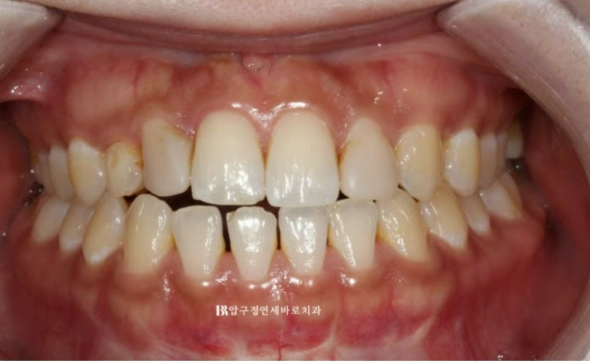

치료 시작 4개월째 교정이 거의 완성된 모습입니다.

유치를 교정 치료 계획에 포함시킬때 가장 중요한 원칙은 유치는 함부로 움직이면 안된다입니다.

유치 특성상 교정력에 잘 반응하지도 않고 엄하게 치근흡수만 일어납니다.

23.05

좌우 라미네이트 두께와 사이즈가 밸런스 있게 제작이 되도록 공간 분배가 끝났고